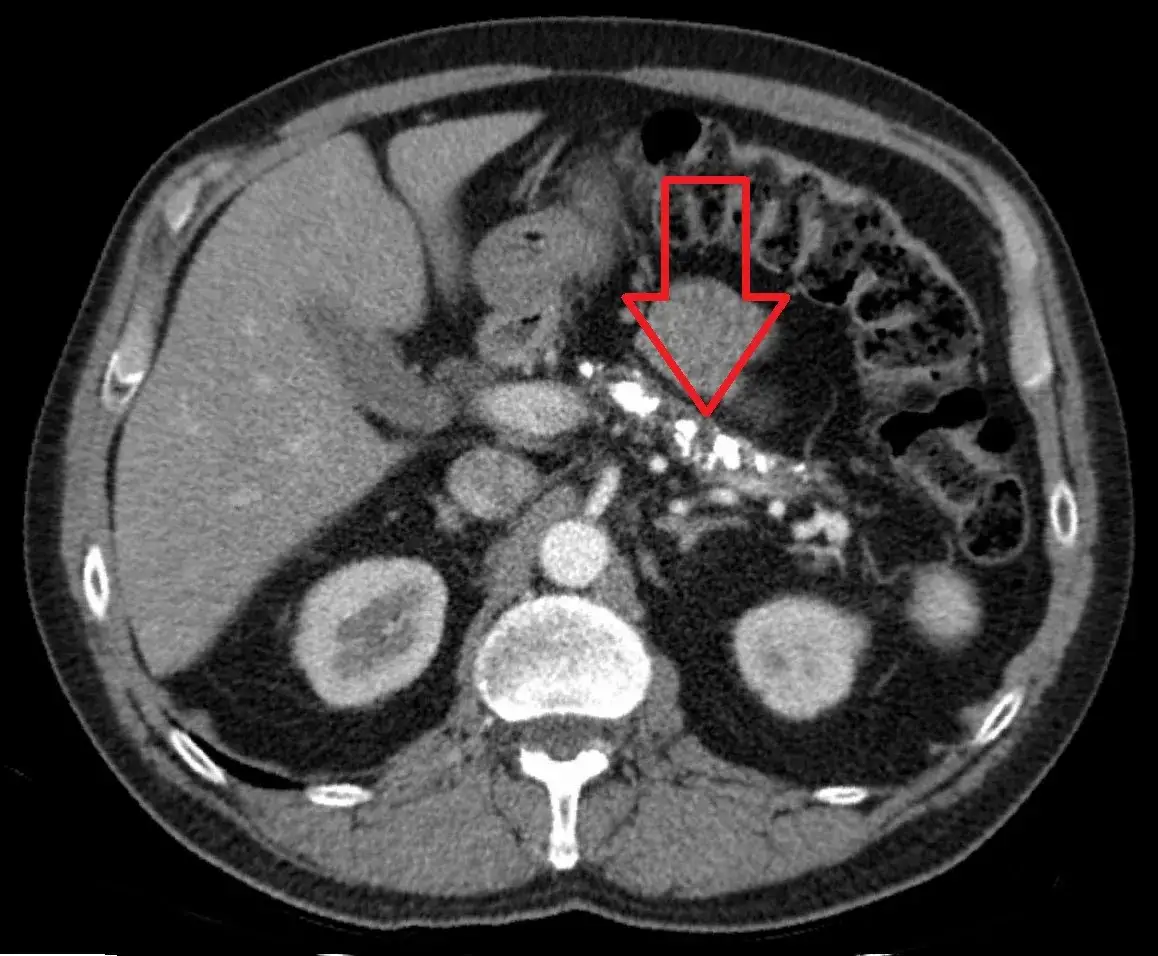

- Tomografia komputerowa (TK) z kontrastem: "Złoty standard" w obrazowaniu trzustki, niezbędny do szczegółowej oceny zmian, zwłaszcza nowotworowych.

Jeśli USG nie daje jednoznacznych wyników lub podejrzewam poważniejsze schorzenie, takie jak nowotwór, sięgam po tomografię komputerową (TK) jamy brzusznej z kontrastem. To badanie jest uznawane za "złoty standard" w diagnostyce obrazowej trzustki. Dzięki kontrastowi mogę precyzyjnie ocenić zmiany w trzustce, ich unaczynienie, a także ewentualne naciekanie okolicznych tkanek czy obecność przerzutów. TK jest niezastąpiona w ocenie powikłań zapalenia trzustki, takich jak martwica czy zbiorniki płynowe.